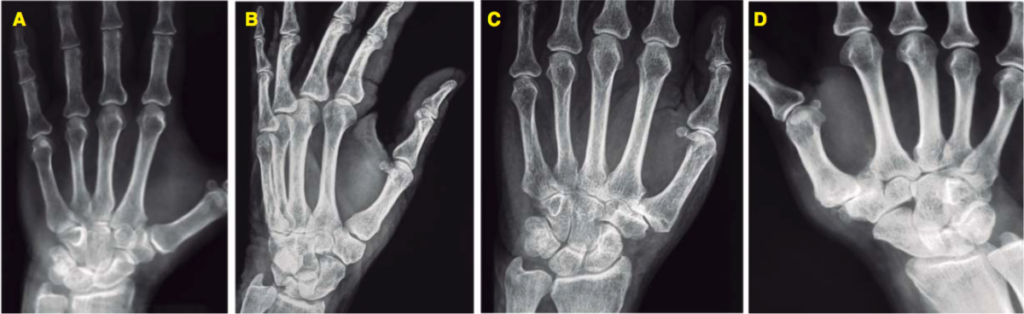

Es la artrosis de la articulacion de la base del dedo pulgar (articulación trapecio-metacarpiana). La rizartrosis es entonces el desgaste del cartilago de la articulación que puede avanzar hasta deteriorar el hueso y los ligamentos de la articulacion de la base del pulgar. Este daño articular es lo que produce dolor en inflamación

La rizartrosis no requiere examenes complejos, ya que el exámen físico y la historia clínica pueden identificar el problema: abrir y cerrar la mano, ubicar la zona de dolor y palpar nódulos y zonas inflamadas. En pocas ocasiones se solicita ecografía, tomografía o resonancia magnética cuando el diagnóstico es confuso o coexiste con otra patología que debamos realizar diagnóstico diferencial. Tambien se pueden solicitar otros examenes de laboratorio para determinar la causa de la rizartrosis.